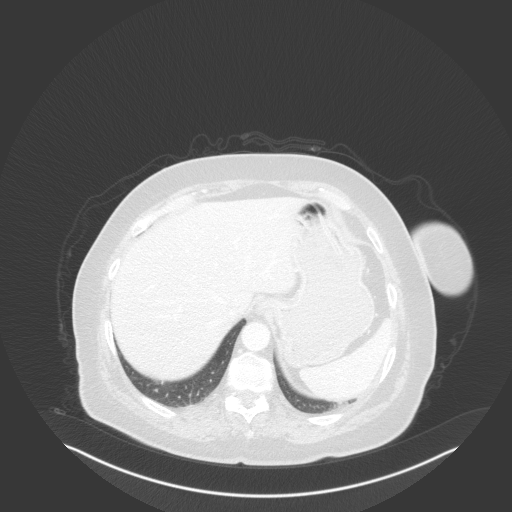

Generated VENOUS CT scan (A→B translation)

Full window (WL 1023.5, WW 4095 β†’ Low βˆ’1024, High +3071)

Lung window (WL -600, WW 1500 β†’ Low βˆ’1350, High +150)

Mediastinum window (WL 40, WW 400 β†’ Low βˆ’160, High +240)